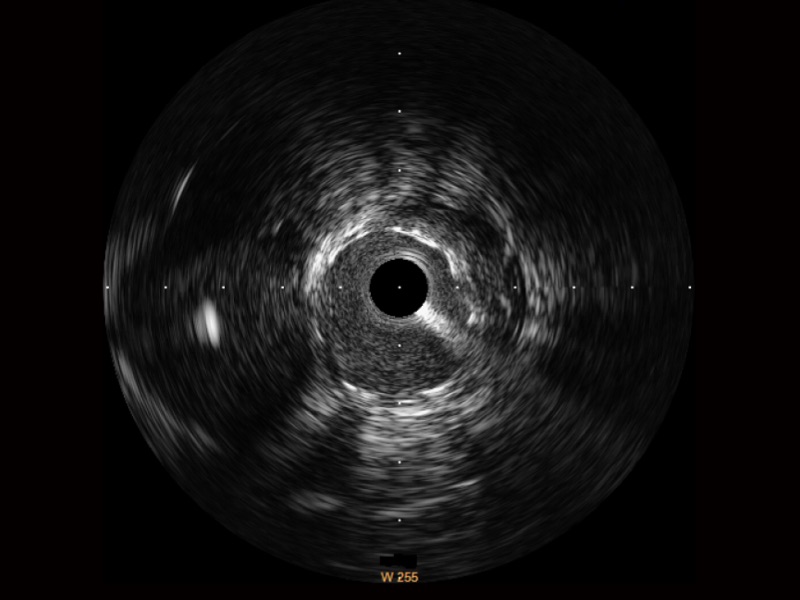

亚星官网宽频IVUS图像

对比传统IVUS导管成像,亚星官网宽频IVUS图像的近场支架梁显影更细腻,远场中膜外血管仍清晰可辨,兼顾远中近,兼顾分辨力与穿透深度